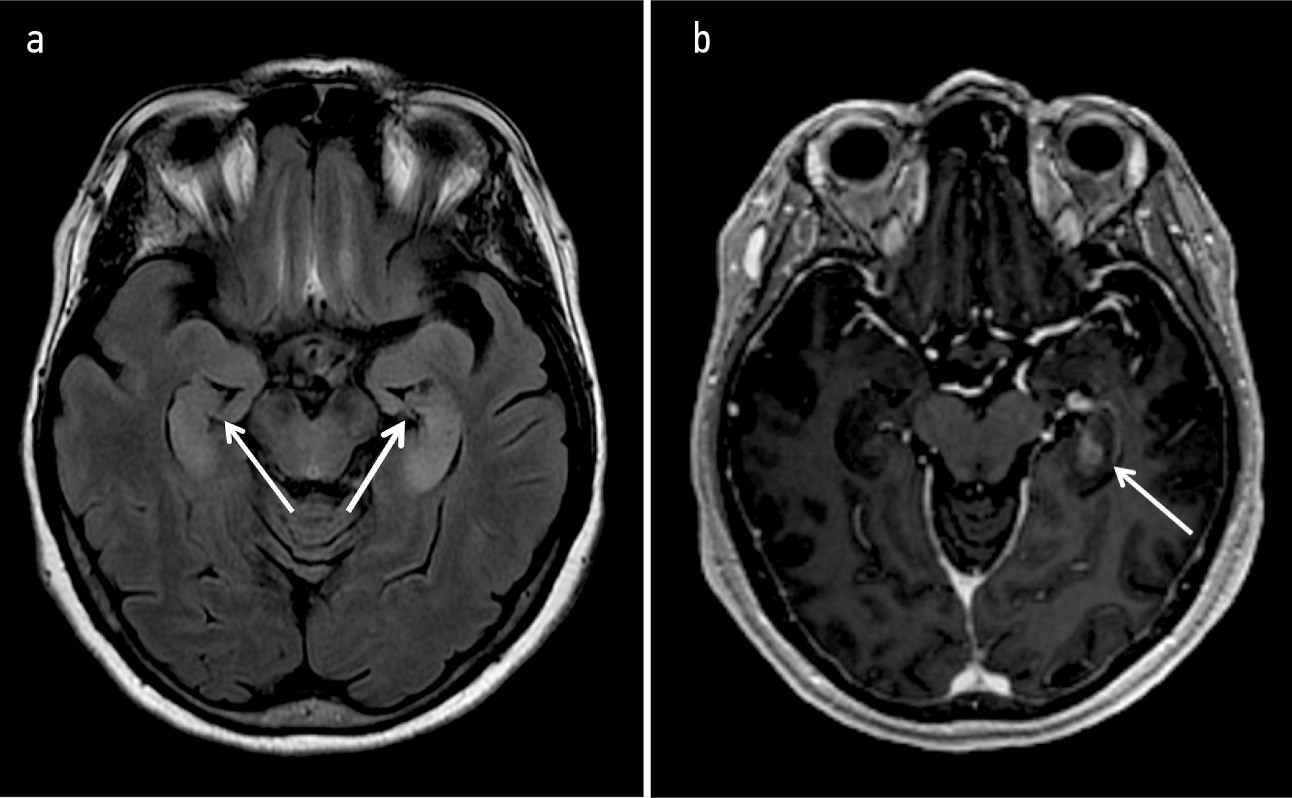

Магнитно-резонансная томография (МРТ) головного мозга с контрастированием от 13.07.2022: МР-картина не позволяет исключить тромбоз правого поперечного синуса. Единичные очаги сосудистого генеза в обоих полушариях головного мозга. Двустороннее изменение сигнала от медиальных височных структур с учетом МР-характеристик может соответствовать лимбическому энцефалиту. Венозная ангиома правой лобной доли. Данных, свидетельствующих о наличии ишемических изменений, не получено (рис. 1).

Рис. 1. МРТ головного мозга с внутривенным контрастированием (13.07.2022): а – диффузное повышение МР-сигнала на последовательностях T2 и FLAIR в области гиппокампа с обеих сторон; b – при внутривенном контрастном усилении определяется накопление контрастного препарата в области левого гиппокампа, МР-картина выявленных изменений характерна для лимбического энцефалита.